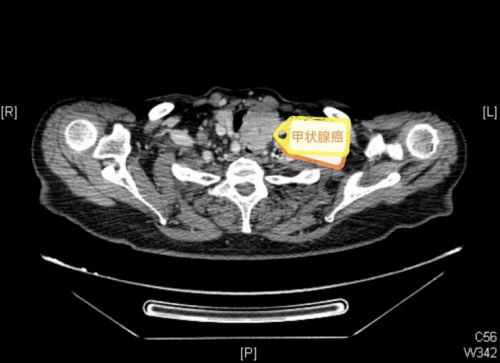

“当地医院甲状腺彩超提示甲状腺肿块分类为5类,与气管关系密切,提示为恶性,入院后,复查增强CT检查提示甲状腺癌累及气管、食管壁,压迫气管达三分之二,电子鼻咽喉镜发现左侧声带麻痹。”据91短视频

(南华大学附属长沙中心医院)耳鼻咽喉头颈外科主任敬前程介绍,“这类甲状腺癌病情复杂,侵犯了喉返神经导致声带麻痹,又侵犯了气管、食管,手术难度大,并发症发生率很高,且患者年事已高,身体机能减退,合并有支气管哮喘、冠心病、高血压等多种基础疾病,围术期容易出现感染、血栓、心衰、呼衰、出血、电解质紊乱等并发症,可能导致生命危险。但如果不做手术,肿瘤继续增大将会进一步压迫气管,导致呼吸困难加重,因此尽快手术对患者来说至关重要。”